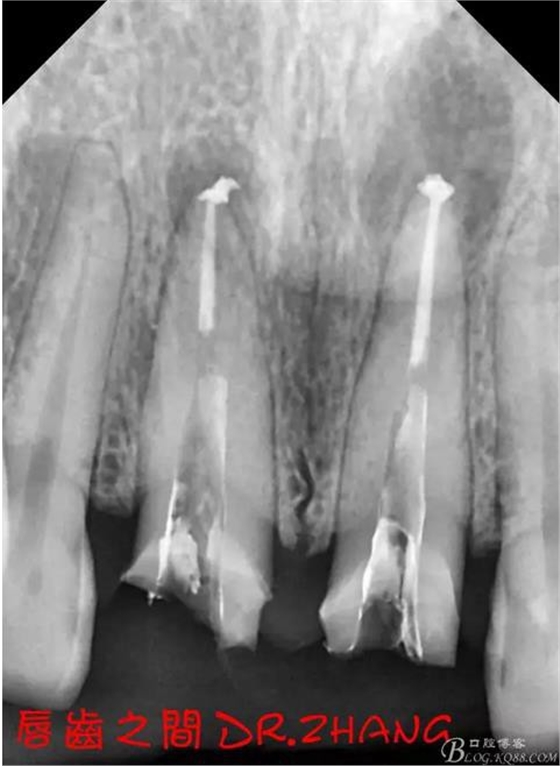

X片示11 21根管內(nèi)有高密度陰影 根尖低密度陰影

診斷:11 21慢性根尖炎

處理:21從修復(fù)體舌側(cè)打開(kāi)通路 髓腔內(nèi)疑似纖維樁 高速和低速手機(jī)聯(lián)合去除樁核 在處理的過(guò)程中不斷拍片確認(rèn)方向 去除樁核后拔髓針去除牙膠 只有一個(gè)標(biāo)尖 膿液大量滲出 雙氧水和鹽水交替沖洗后 滲出減少 開(kāi)放髓腔 隔日復(fù)診